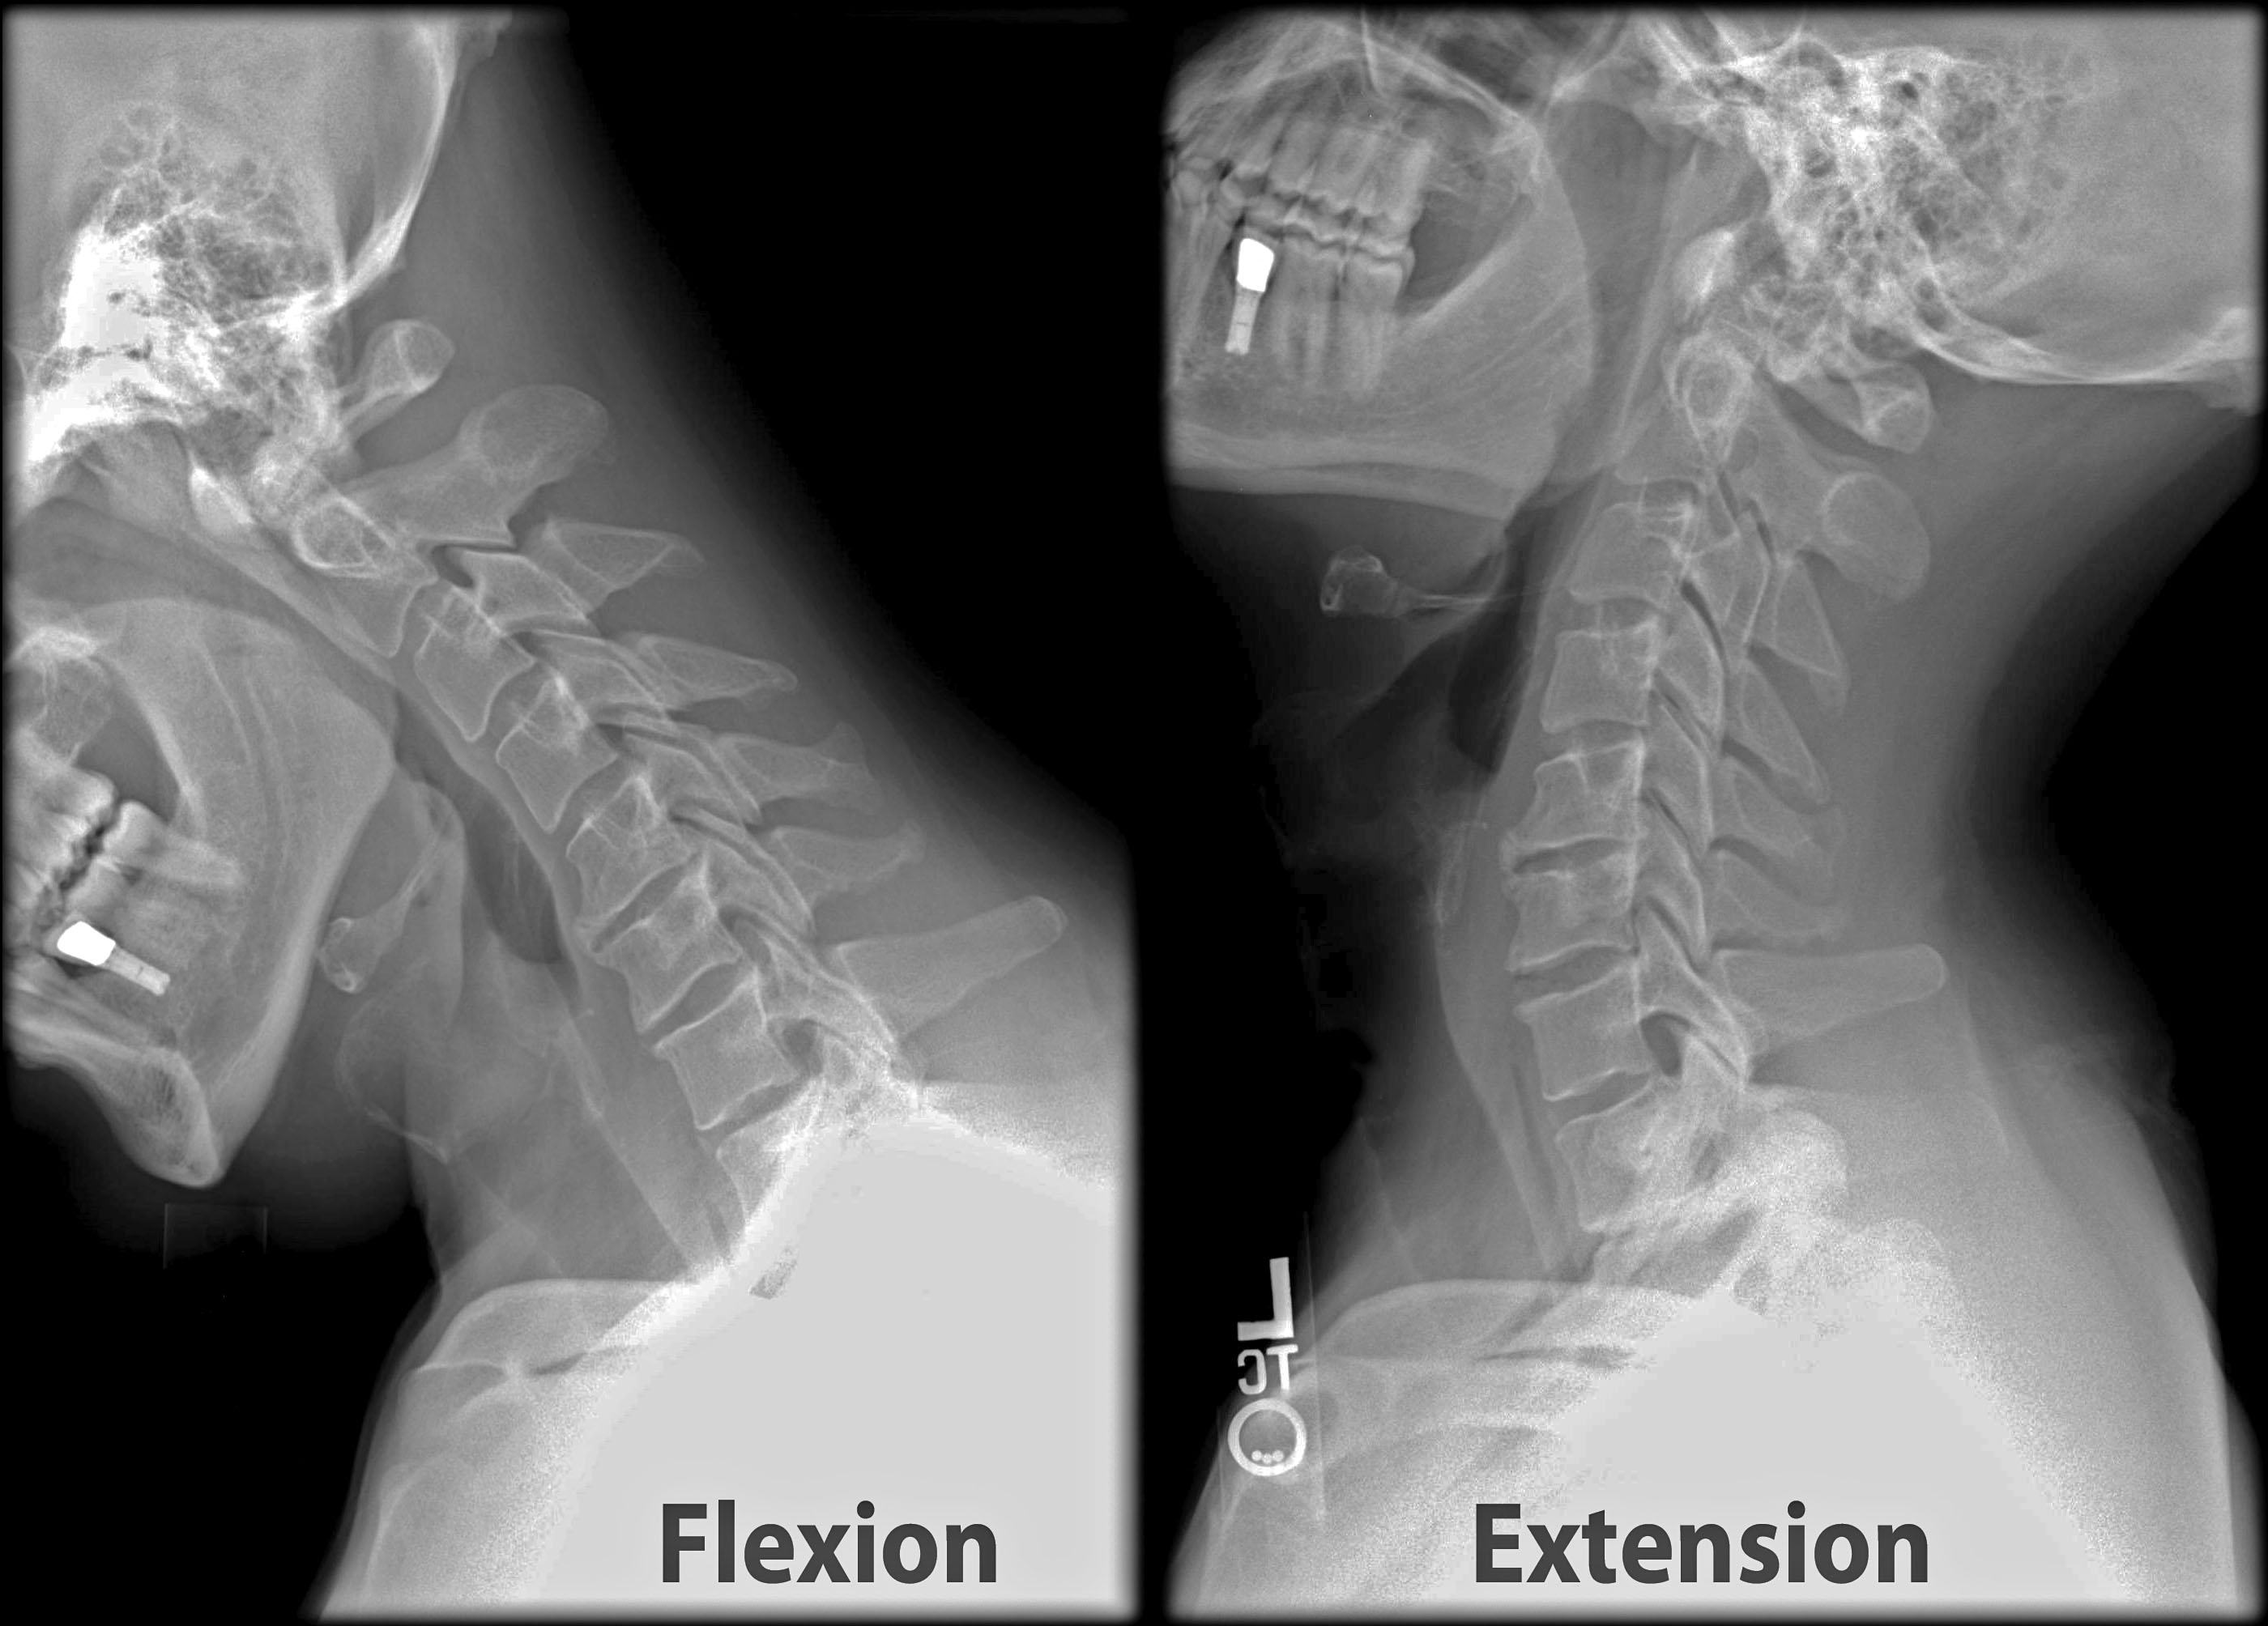

이 신호의 핵심 원인은 바로 **전방머리자세(Forward Head Posture, FHP)**입니다.

머리가 어깨보다 앞으로 빠져 있는 이 자세는 흔히 ‘일자목’, ‘거북목’이라고 불리며, 현대인에게 너무나 익숙한 모습이 되었습니다. 문제는 이 자세가 단순히 목만 불편하게 만드는 것이 아니라, 뇌로 가는 혈류를 방해하고 신경을 압박하여 두통·현훈·구토까지 이어질 수 있다는 점입니다.

특히 청소년·대학생은 근골격계가 완전히 발달하지 않았기 때문에, 장시간 전방머리자세가 경추의 곡률(Cervical Lordosis)을 무너뜨리고 조기 퇴행성 변화를 불러옵니다.

좁은 좌석, 전방 주시 자세, 차량 진동은 모두 **두개-척추각(CVA, Craniovertebral Angle)**을 줄여 거북목을 심화시키는 요인입니다.

운전 시 시야 확보를 위해 턱을 앞으로 내밀게 되는데, 이때 후두하근이 경직되고 경추 1–2번 주변의 신경총을 압박합니다. 그 결과, 두개골 기저부에서 시작되는 두통이 뒤통수와 관자놀이로 번져갑니다.

한 신경외과 교수는 “CVA가 작을수록 현훈 지수(DHI)가 높아지고, 경추 고유수용성 오류(JPE)가 증가한다”며, 목이 앞으로 나가면 단순 통증이 아니라 균형감각과 신경계 정확성까지 무너진다고 설명합니다.